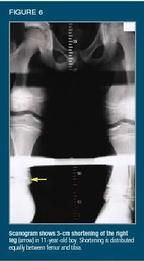

Case 5: An 11-year-old boy walks "funny." The boy's father brought him in for examination because he had been "walking funny" for several years. He had no history of physical trauma or clinically significant illness. Gait analysis revealed a grossly obvious limp manifested by vaulting over the left leg and stepping down (as into a hole) on the right leg.

Physical examination showed an apparently healthy child who was limping. Scoliosis was apparent when the child was standing, and tape measurement showed his right leg to be 3 cm shorter than the left.

Results of a neurologic examination were normal, and all joints showed full range of motion. The left leg felt slightly warmer to the touch than the right leg, but the skin appeared normal.

Radiographs showed normal-appearing physes and bony architecture, but scanograms confirmed 3-cm shortening of the right leg: Half the shortening was in the femur; half, in the tibia (Figure 6). The final diagnosis was hemihypertrophy of the left leg as a result of deep-seated arteriovenous fistulae.